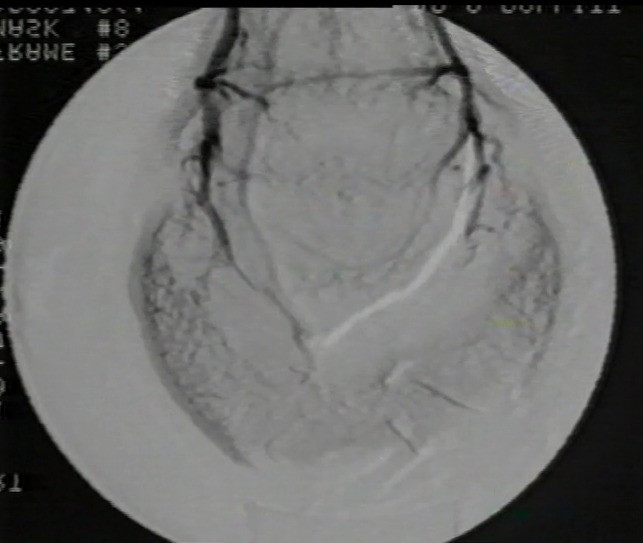

Bilden nedan visar en sådan skada på en häst som till slut avlivades (år 2024).

Veterinären tyckte att de såg en hovbensfraktur som aldrig läkte, hästen slutade inte att halta. Dissektionen visade sanningen. Läs mer (fb inlägg) >>

FILM på fb som visar skada; https://www.facebook.com/HoofStudies/videos/1084758205678977/